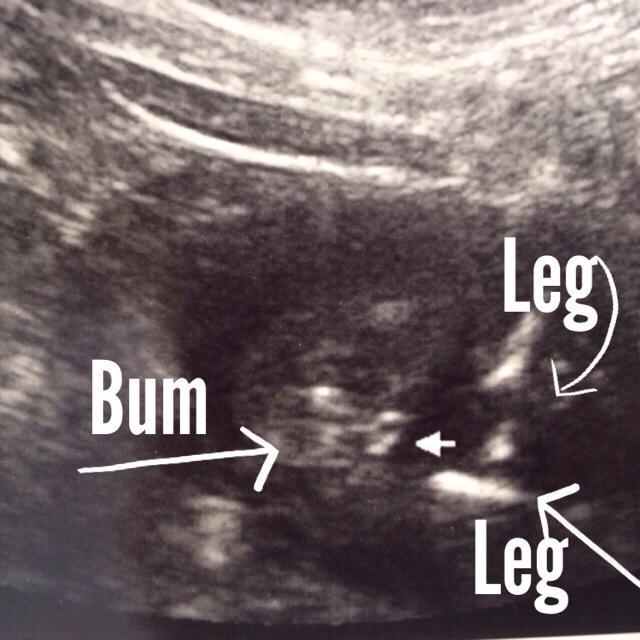

This is at 16 weeks, 2 days. The tech told us she was 75% certain (with a 100% track record) and the OB look at it and said she was 100% certain the tech was right. Just looking for a bit of confirmation. I tried to mark the picture as best as I could. This is a shot looking up from the bottom as if you were changing a diaper.